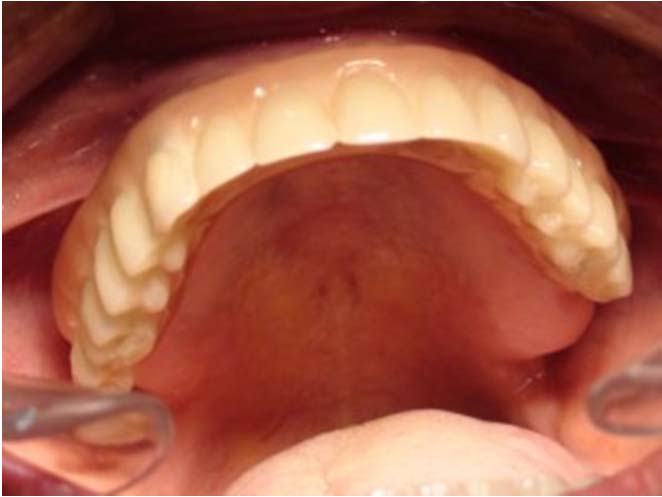

Bezzubá čelist

Pevné můstky – lepené nebo šroubované

Třmeny

Kulové attachmenty

Sub-Tec Locator®

Metoda All-on-four

Bezzubá čelist je hlavní indikací pro ošetření pomocí implantátů. Zejména celkové zubní náhrady v dolní čelisti mají velice nízkou stabilitu a držení díky velkému úbytku kosti.

S pomocí zubních implantátů můžeme díky různým kotevním systémům (třmeny, kulové hlavy, Locatory) zajistit stabilitu a držení protézy nebo při použití většího počtu implantátů zhotovit pevné náhrady – můstky nalepené nebo našroubované na pevno na implantáty.

S těmito typy náhrad můžeme dosáhnout perfektní funkci, výbornou estetiku, fonetiku a současně zajistit u pacienta možnost dobré hygienickou péče a čištění, která je pro životnost implantátů velice důležitá.